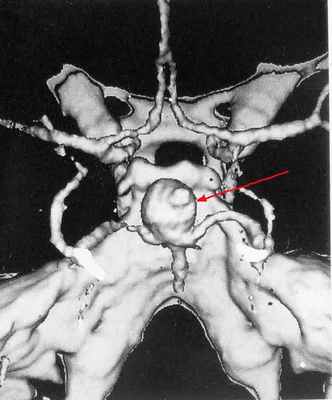

ЗD-KT ангиография - мешотчатая аневризма развилки основной артерии

4. Более 25 мм – гигантские.Велизиев круг (артериальный круг головного мозга) с гигантской аневризмой внутренней сонной артерии (слева

Велизиев круг (артериальный круг головного мозга) с гигантской аневризмой внутренней сонной артерии (слева)